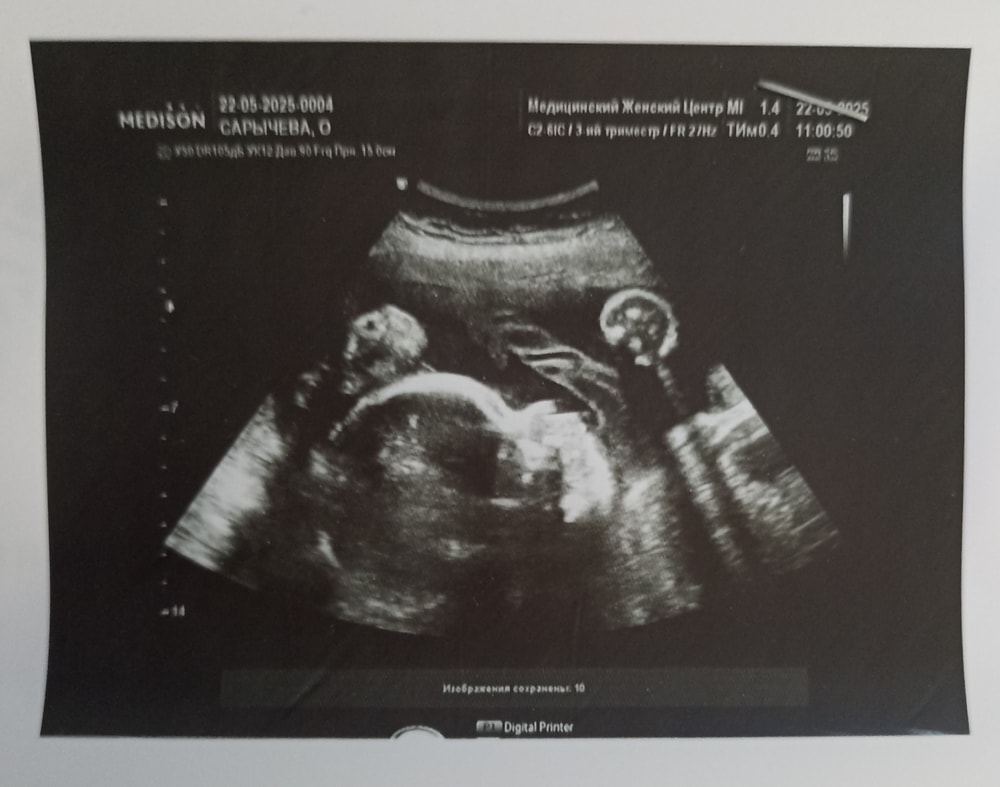

29 недель

Анализы, скринингиНам 29 недель. Были мы на экспертном УЗИ в Москве, так же сдали анализы для приема профессора Бицадзе. Дозу Клексана увеличили до 0.8 в сутки.

Профессор сказала, наша главная задача доходить до 34 недель, а там уже доставать малышку безопасно.